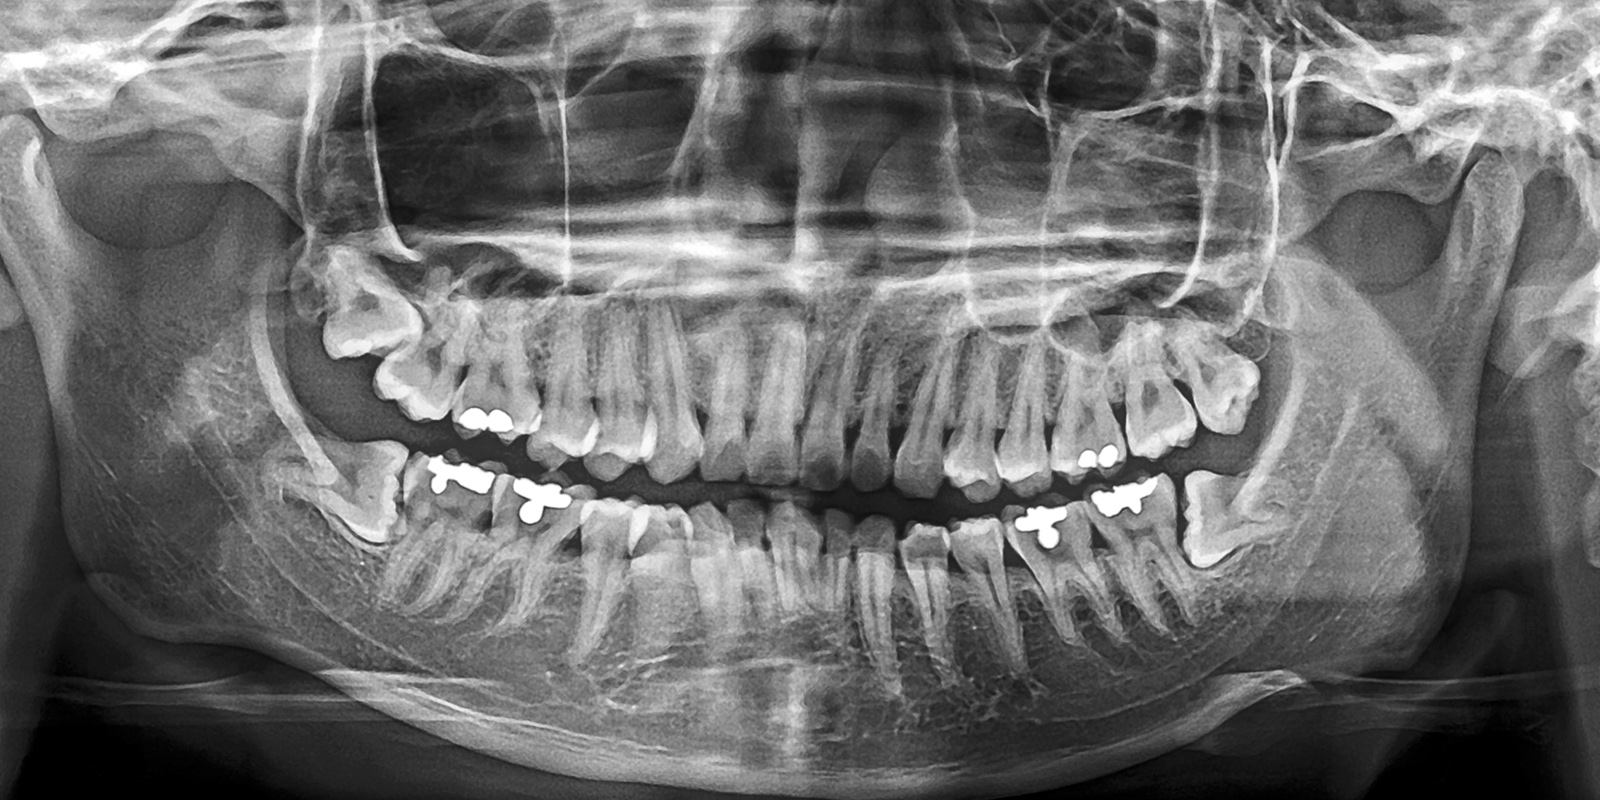

「パノラマレントゲン」で全体を把握

パノラマレントゲン」は、副鼻腔から顎まで、上下の歯を1枚の画像に収めることが可能な機器です。この画像で親知らずの位置や向き、そして周囲の歯との関係をひと目で確認できます。

特に下顎の親知らずは、下歯槽神経という大切な神経の近くに位置することが多く、抜歯による神経損傷のリスク評価が非常に重要です。パノラマ撮影による画像で、親知らずと神経との距離や重なり具合を事前に把握することが可能です。